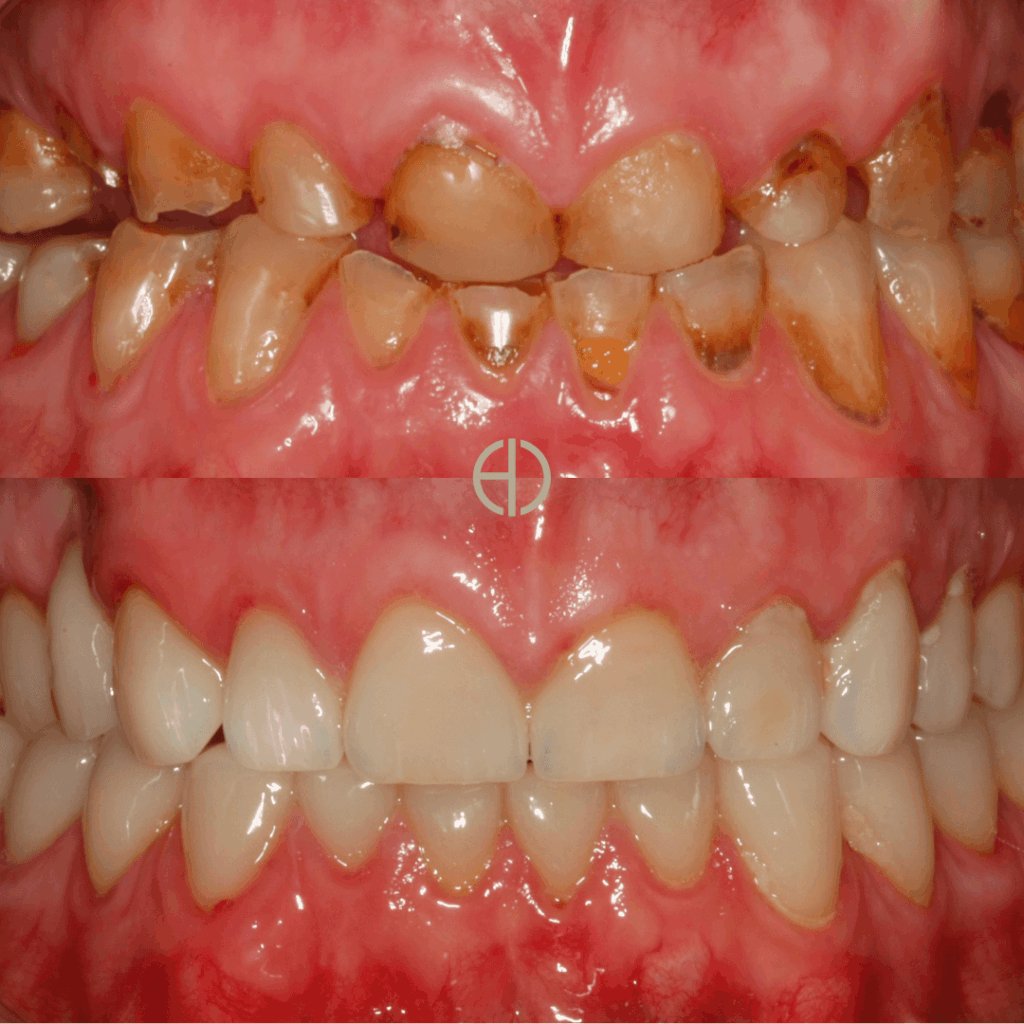

Example Before and Afters:

Example #1